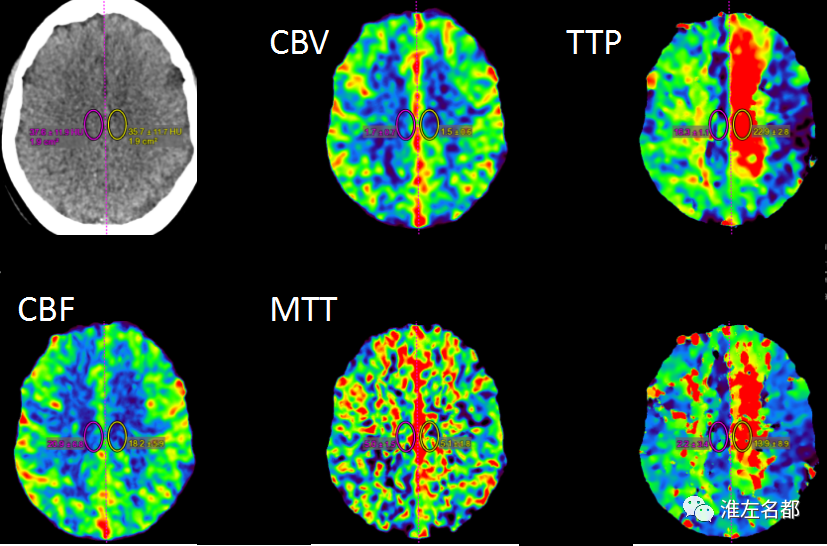

△脑CTP:左侧大脑前动脉区TTP较对侧显著延长,但其大部分区域CBV和CBF未见明显降低。

1.最后表现正常-到院时间达7小时余,超出静脉溶栓时间窗。2.NIHSS-14,左侧大脑前动脉闭塞,其供血区TTP较对侧显著延长,但其大部分区域CBV和CBF未见明显降低,提示较大范围“组织窗”,可考虑急诊血管内治疗。